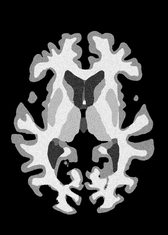

4.2 Registration to a 100 micron ex-vivo brain MRI volume

To showcase the efficacy of our method on real large scale images, we register a 250 in-vivo MRI image (Lüsebrink et al., 2017) to a 100 ex-vivo FLASH human brain volume (Edlow et al., 2019). This represents an inverse problem with more than 11.2B optimizable parameters (compared to 20M for clinical datasets), or 44.8GB of GPU memory. The entire problem does not fit on most GPUs, necessitating distributed multimodal registration. We optimize a composite transform - affine followed by a diffeomorphic mapping; details can be found in Section E.1. Multimodal deformable registration took 58 seconds on 8 NVIDIA A6000 GPUs, which is unprecedented at this resolution. Fig. 6 shows qualitative results, highlighting the ability to register highly detailed structures such as cerebellar white matter; these structures are not visible at macroscopic scales. The resultant advantages of performing registration at this scale can allow researchers to characterize the neuroanatomy at microscopic resolutions and allow morphometric analysis of cortical layers and subcortical nuclei among other structures.